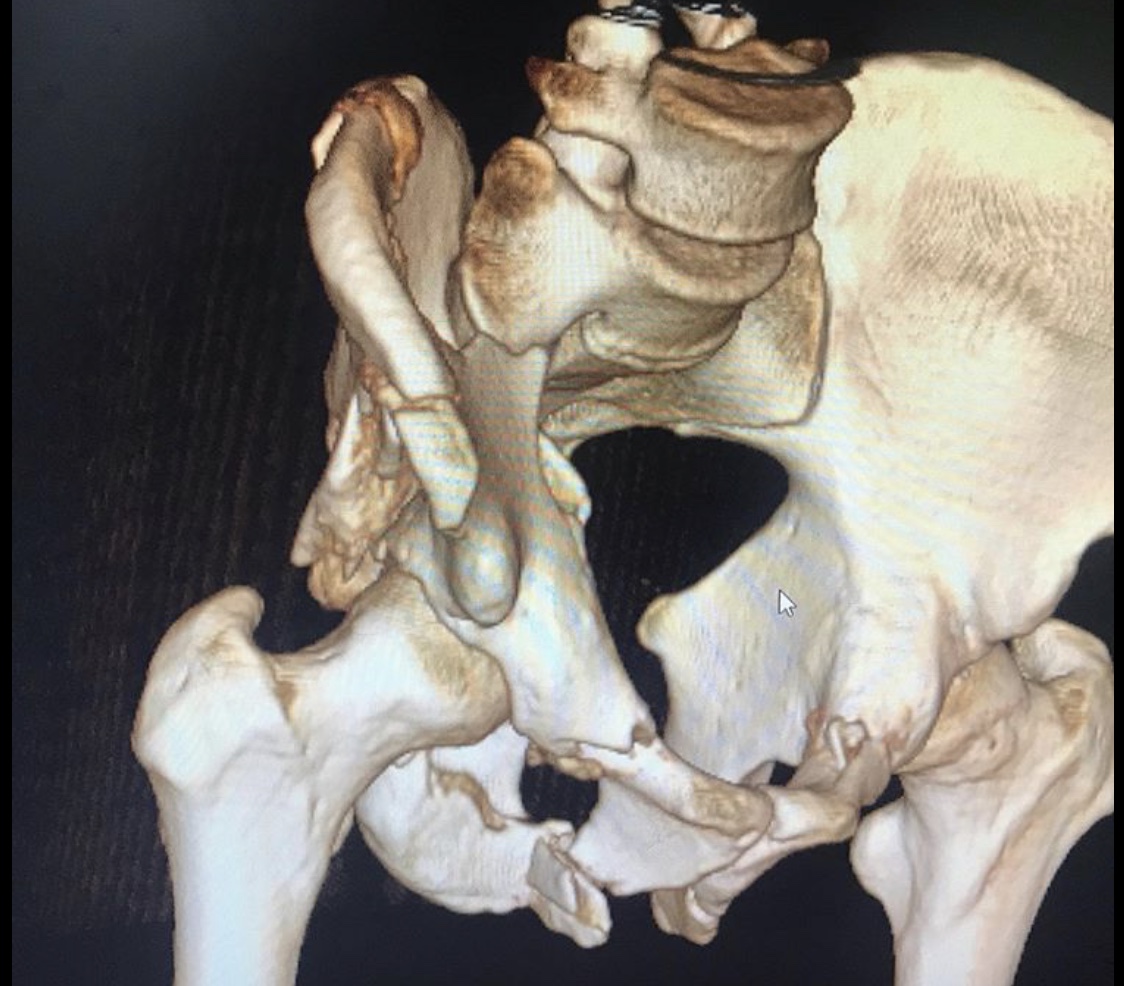

Перелом таза – тяжелейшая травма костей скелета, уступающая по опасности только травмам позвоночника и черепа. Она отличается особой опасностью, так как ее сопровождают обильная потеря крови и шока. Пострадавшему требуется экстренная врачебная помощь, иначе высок риск гибели. Даже при срочном врачебном вмешательстве не всегда удается спасти пострадавшего, который может погибнуть от кровопотери или осложнений болевого травматического шока.

Но к врачам-травматологам Городской клинической больницы № 7 Казани этот пациент поступил лишь спустя месяц после травмы. Врач – травматолог клиники Руслан Закиров признается: «Они в другом городе лечились. Жизнь спасали. К сожалению, не во всех больницах есть возможности для хирургии таза».

Пациента, что называется, «собрали».

Была выполнена открытая репозиция, остеосинтез пластинами.